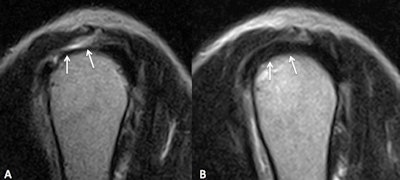

Sagittal T2-weighted MR images of the shoulder. Focal lesion (arrows) is shown on left (A). Image taken two years later (B) shows evidence of healthy rotator cuff tendon.He acknowledged a number of limitations to the study. Patients were not divided by age, and the medical and physical therapy was not standardized. In addition, the researchers did not quantify the degree of improvement or worsening of the tendinopathy on imaging, he said.